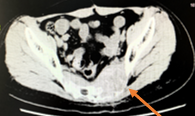

2019年1月28日CT:

2019年3月14日CT:

转移灶评估:肺内病灶增大、增多

病情评估:PD

PFS:1.4个月